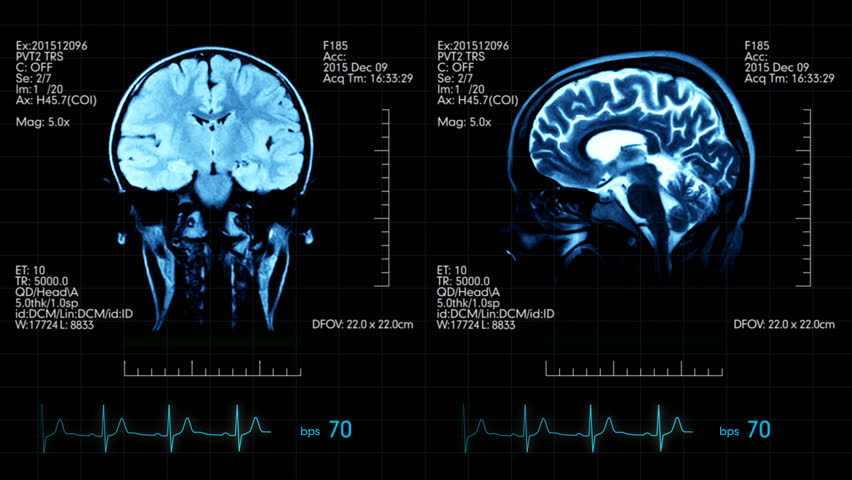

脑部扫描

脑部扫描是脑部研究和医学中必不可少的工具,可帮助理解和识别脑部各个区域的问题或障碍。脑部扫描类型可以包括计算机断层扫描(CT)扫描,磁共振成像(MRI)扫描,正电子发射断层扫描(PET)扫描,磁脑图(MEG)扫描等等。MRI扫描技术在提供诸如大脑和组织图像之类的数据方面不同于X射线。

某些类型的脑部扫描可分为结构性脑部扫描或功能性脑部扫描。结构性脑部扫描(例如MRI扫描)处理大脑的结构。这些扫描可以显示不同组织之间的对比,例如脑脊液,灰质,白质等等。研究人员使用它们来了解大脑的解剖结构。功能性脑部扫描用于间接测量脑部功能,例如神经活动。